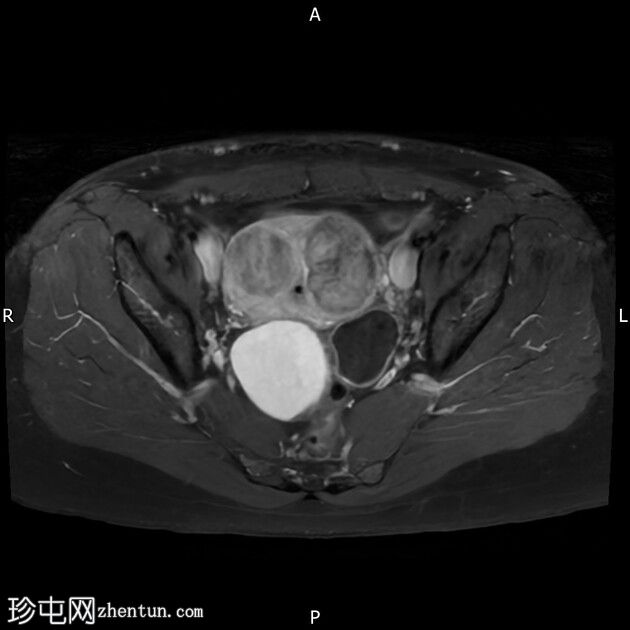

轴位

T2加权像

右侧卵巢囊肿,T2加权像呈低信号,T1脂肪抑制像呈高信号,大小为6 x 5.2 cm,符合子宫内膜异位囊肿的影像学表现。

左侧卵巢囊肿,T2加权像呈低信号,T1脂肪抑制像呈高信号,符合子宫内膜异位囊肿的影像学表现。

双侧卵巢粘连于后道格拉斯窝,呈“接吻卵巢征”。

多发性子宫肌瘤。宫内放置宫内节育器。

结论:双侧卵巢子宫内膜异位囊肿。多发性子宫肌瘤。

本病例显示右侧卵巢子宫内膜异位症,左侧卵巢囊肿内含出血性物质,并可见“接吻卵巢征”,诊断为卵巢子宫内膜异位囊肿伴可能粘连/深部盆腔子宫内膜异位症。

此外,还存在子宫肌瘤。